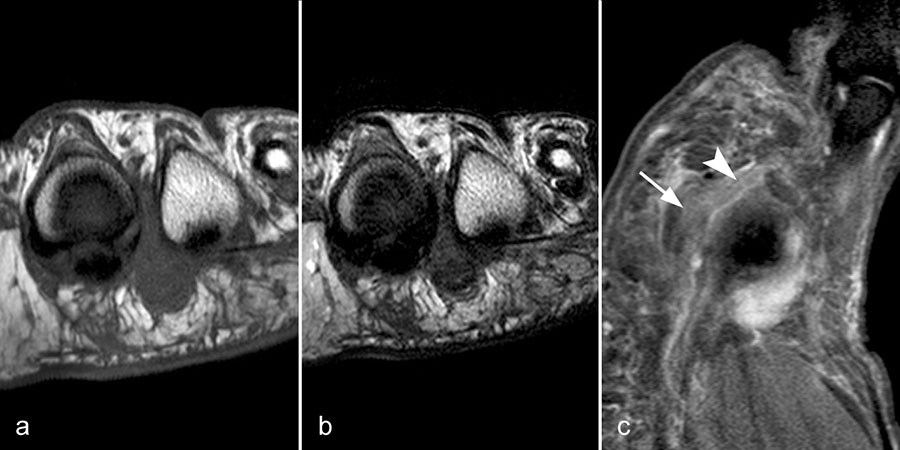

Gicht

Typische Gichtmanifestation an der Großzehe mit Tophusstachel (Pfeil) und großem Tophus, in welchem Uratablagerungen identifiziert werden können (Pfeilspitze). T1-gewichtete Sequenz vor (a) und nach (b) Kontrastmittelgabe, letztere mit Fettsuppression.

Abbildung 15

Dies erst recht, wenn diese Arthritis am Großzehen­grundgelenk auftritt (Abb. 15). In diesen Fällen sollte man den Verdacht auch dann aufrechterhalten, wenn die MRT nur eine unspezifische Entzündung zeigt und die Harnsäurewerte, die starken Schwankungen unterliegen können, nicht erhöht sind.

Spezifische MR Befunde finden sich erst bei der chronischen Gicht, wenn sich in T2 sehr signalarme Kristallablagerungen und Gicht-Tophi bilden. Letztere führen dann häufig zu den aus der Röntgendiagnostik bekannten gelenkfernen Erosionen.

Abbildung 15: Typische Gichtmanifestation an der Großzehe mit Tophusstachel (Pfeil) und großem Tophus, in welchem Uratablagerungen identifiziert werden können (Pfeilspitze). T1-gewichtete Sequenz vor (a) und nach (b) Kontrastmittelgabe, letztere mit Fettsuppression.